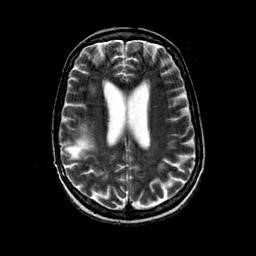

На Т2-зависимых томограммах в белом веществе обнаруживаются:

- диффузные поля гиперинтенсивного сигнала без четких границ, одно- или двухсторонние;

- либо очаги 1-3 см в диаметре.

Типично расположение очагов воспаления в валике мозолистого тела. Дифференциальную диагностику необходимо выполнять с прогрессирующей мультифокальной лейкоэнцефалопатией и лимфомой.

Лабораторные и инструментальные исследования направлены в основном на исключение других причин неврологических нарушений. МРТ предпочтительнее, чем КТ; нередко она выявляет очаговые диффузные изменения повышенной плотности в белом веществе головного мозга. Эти изменения указывают на лейкоэнцефалопатию.

Кроме того, иногда наблюдаются атрофия вещества мозга с расширением желудочков и борозд мозга. Однако ни один из этих симптомов не специфичен для ВИЧ-энцефалопатии. Кроме того, иногда МРТ при ВИЧ-энцефалопатии никаких изменений не выявляет. В отличие от прогрессирующей мультифокальной лейкоэнцефалопатии очаги в белом веществе не распространяются на корковые U-волокна, т.е. не достигают коры. Отек, сдавление тканей и усиление контраста для ВИЧ-энцефалопатии не характерны и должны навести на мысль о других заболеваниях.